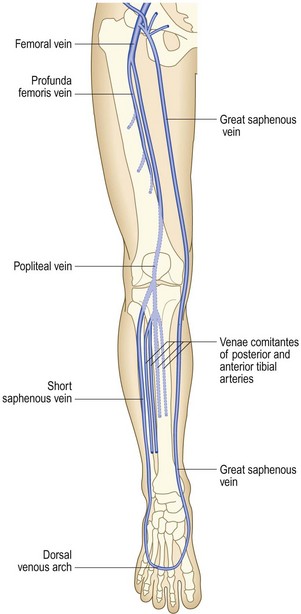

The great (long) saphenous vein passes anterior to the medial malleolus at the ankle, up the medial aspect of the calf to behind the knee, then up the medial aspect of the thigh to join the common femoral vein in the groin at the saphenofemoral junction (Fig. 6.41).

The lesser (short) saphenous vein passes behind the lateral malleolus at the ankle and up the posterior aspect of the calf. It commonly joins the popliteal vein at the saphenopopliteal junction, which usually lies 2 cm above the posterior knee crease.

There are numerous intercommunications between the long and short saphenous, and between the deep and superficial venous (via perforating or communicating veins) systems; and the venous anatomy of the leg is highly variable.